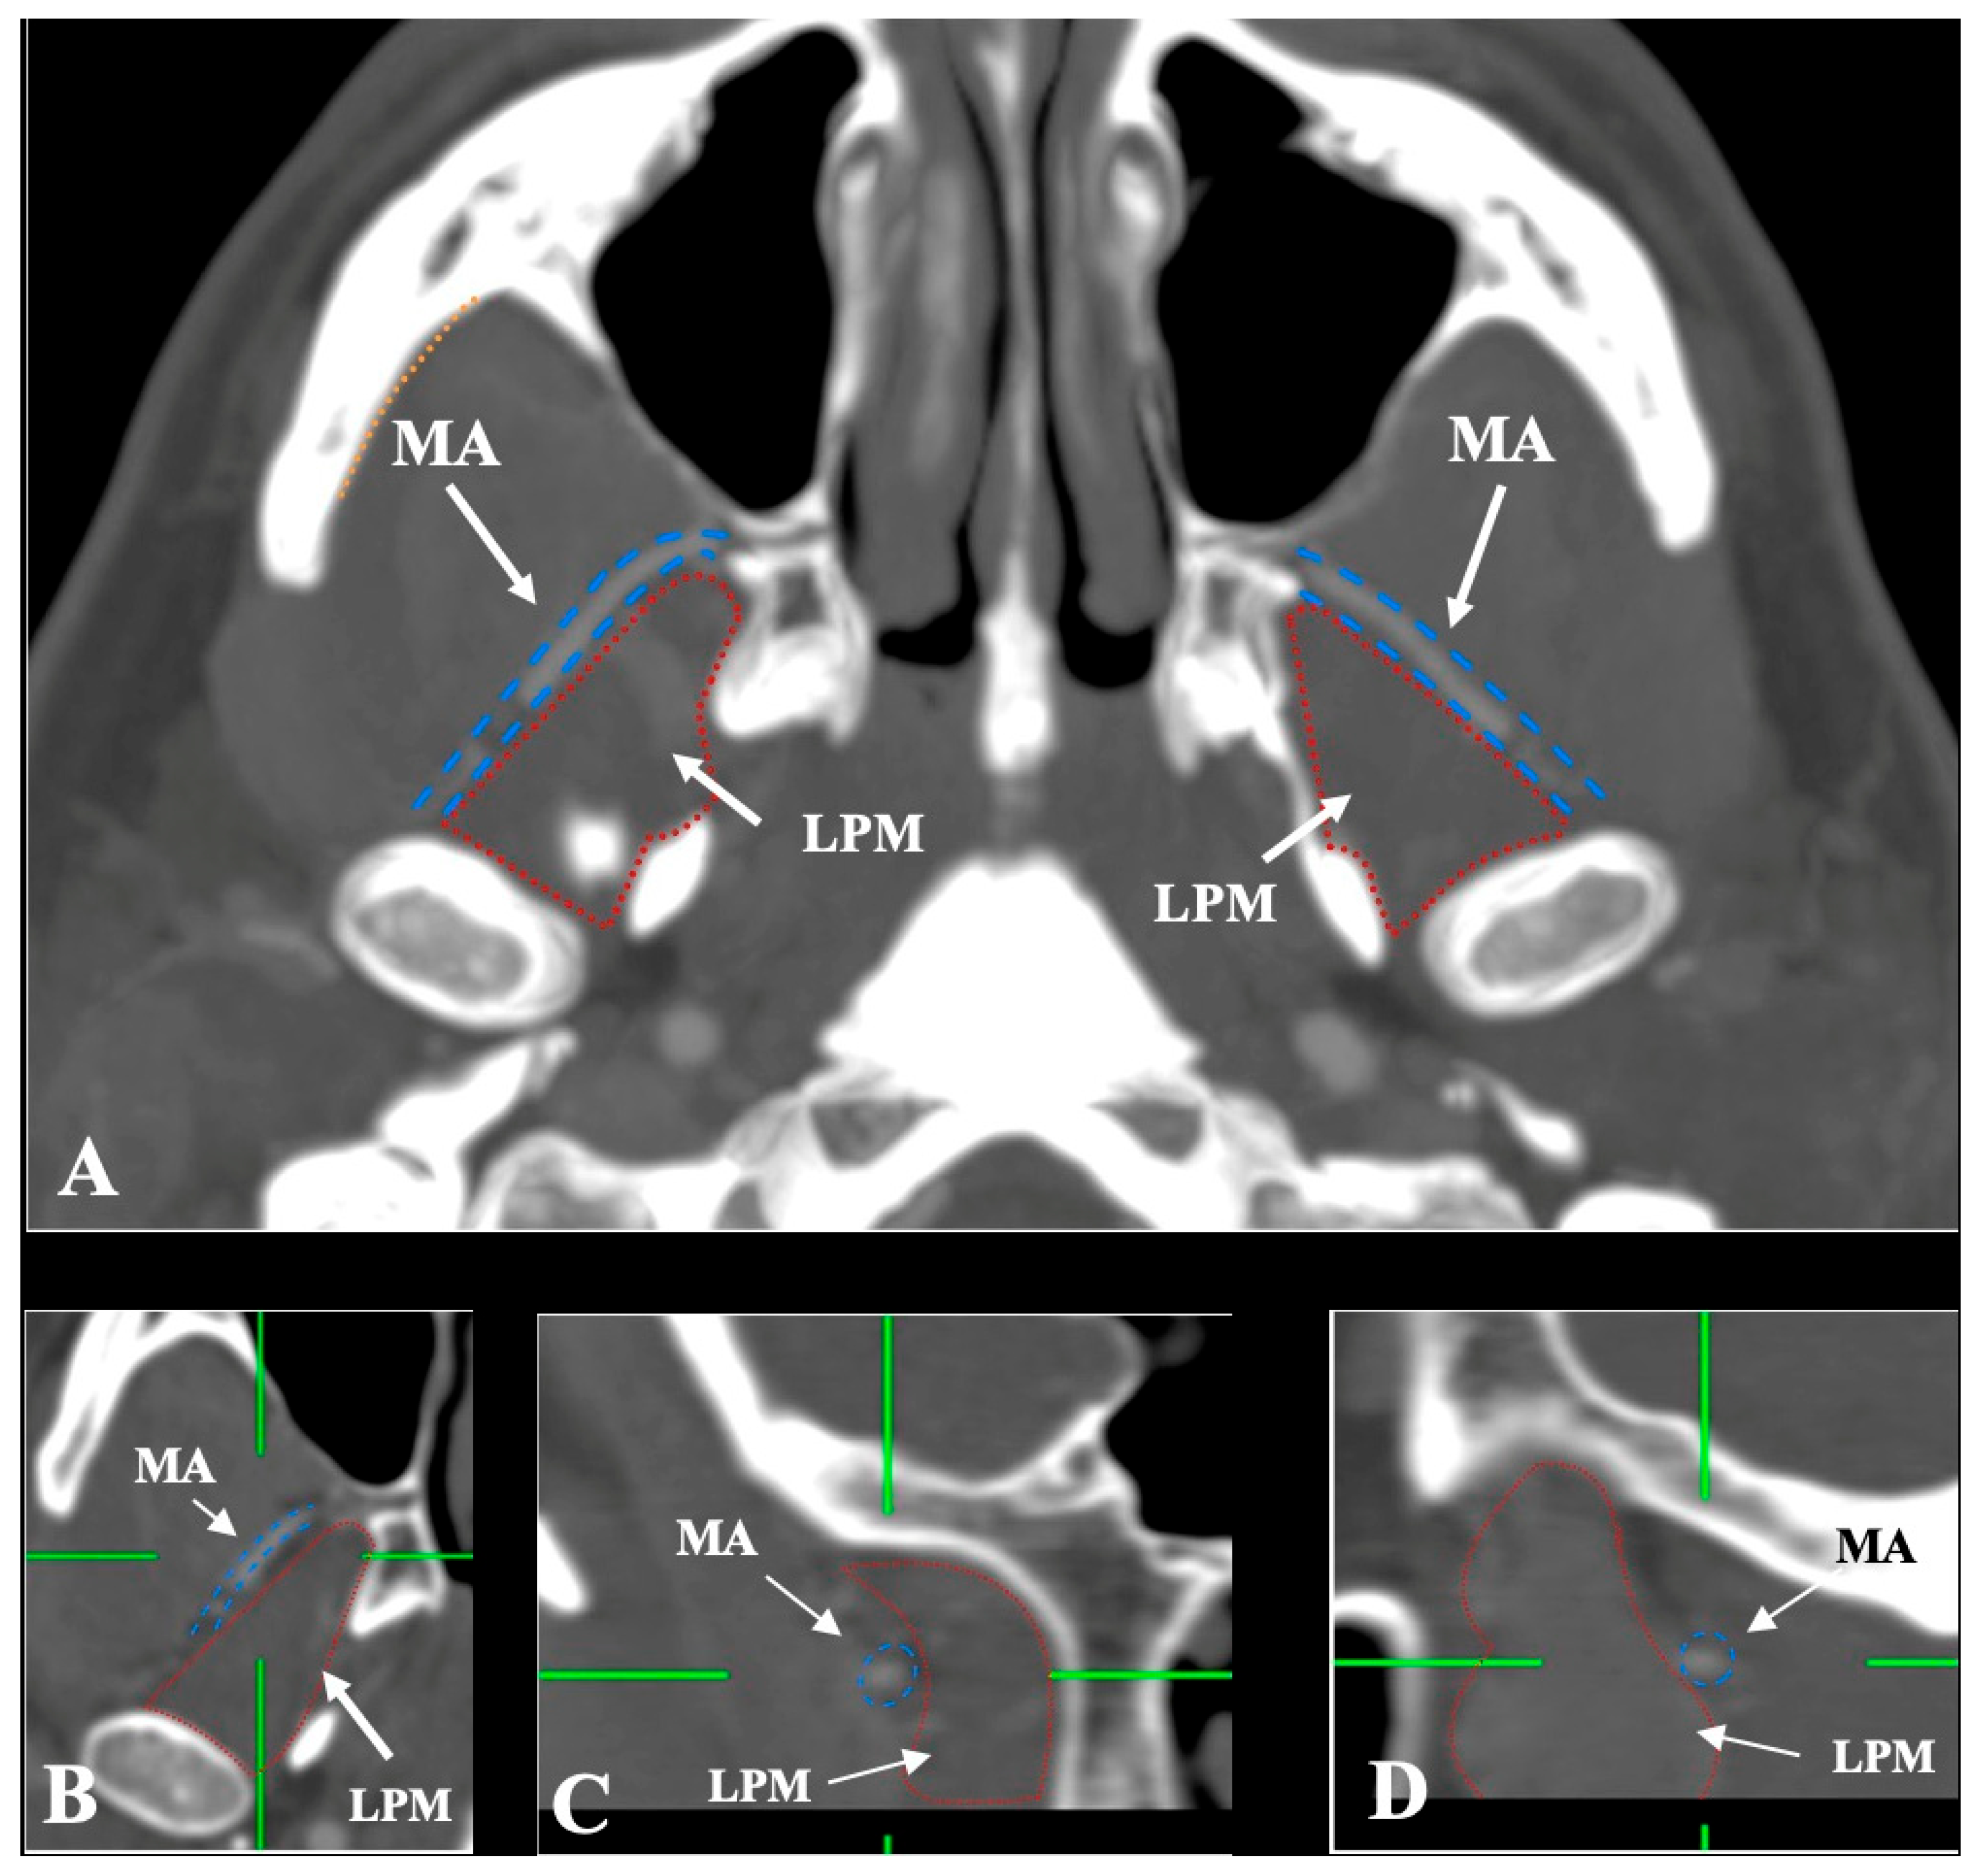

- Lateral (superficial) to the LPM: Detected in 321 sides (64.2%). This configuration was consistently visualized in axial, coronal, and sagittal planes (Figure 2).